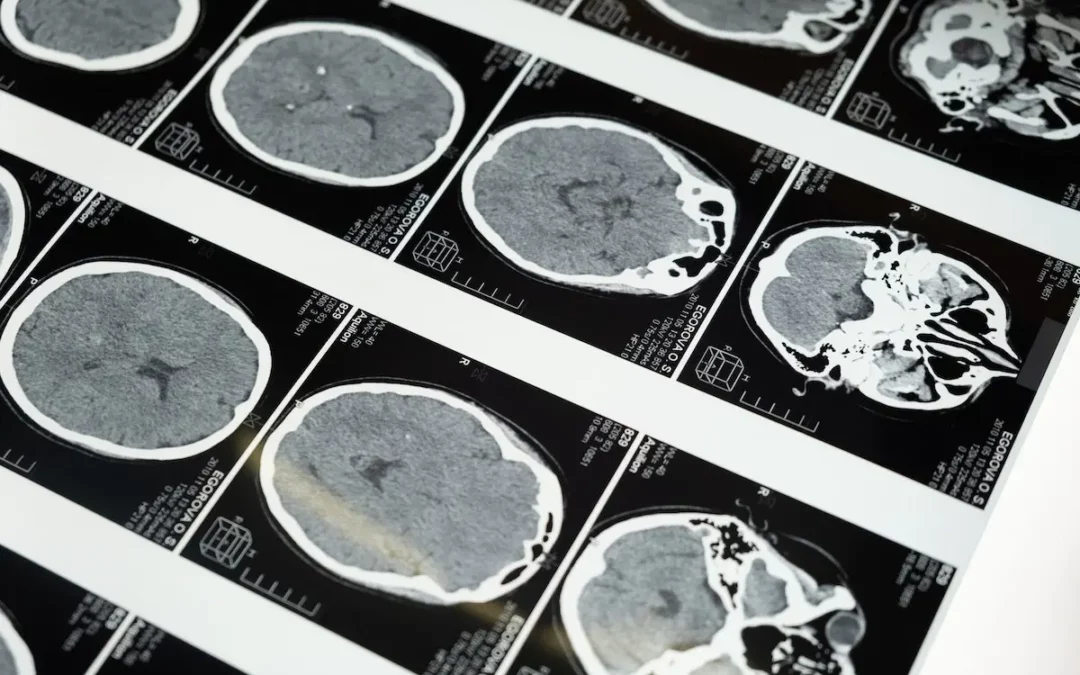

There’s newfound hope in the battle against Alzheimer’s and dementia. A groundbreaking study led by Dr. Paul Harch, Director of Hyperbaric Medicine at LSU, and Dr. Edward Fogarty, a physician in North Dakota, has revealed impressive improvements in brain...